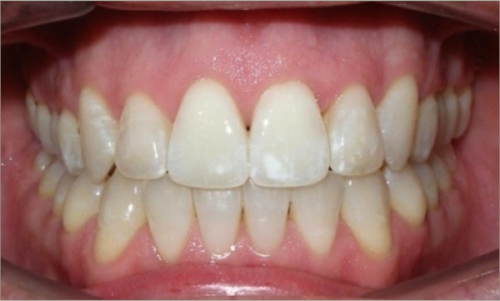

30 year old male:

Diagnosis:

- Upper and lower crowding

- Narrow upper & lowerarch forms

- Open bite

Treatment:

- Invisalign

- Non-Extraction

- 27 months